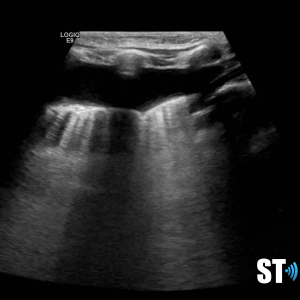

Normal lung ultrasound shows a clean linear pleural line with A-lines (multiple horizontal reverb artifacts) and lung sliding with respiration.

Horizontal reverb artifacts at equidistant intervals from pleural interface.